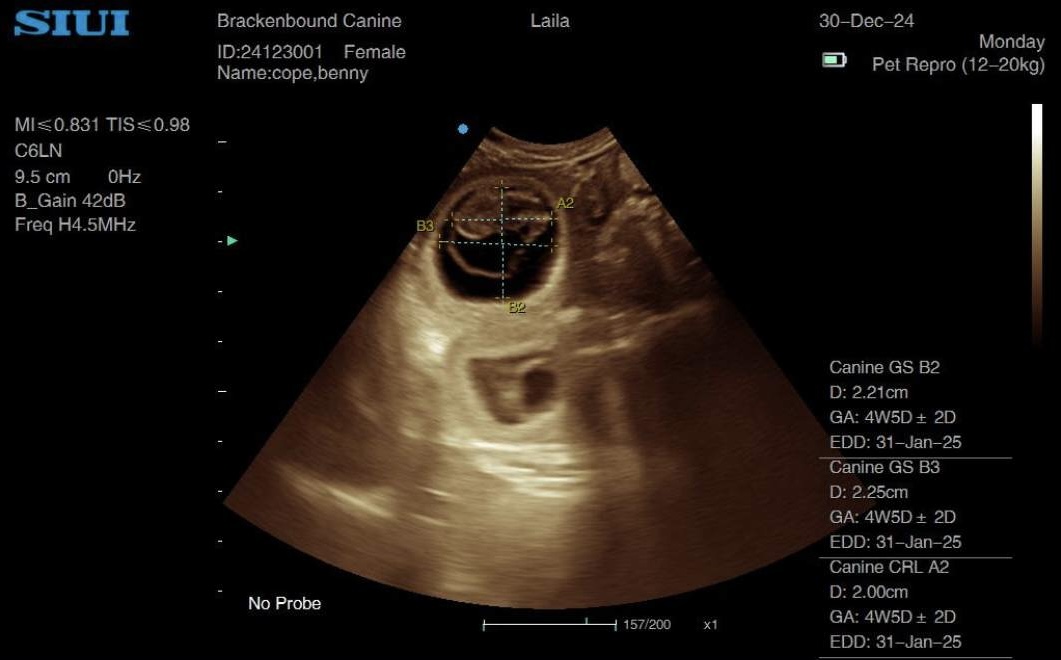

I used both GSD and CRL measurements on 2 different embryos to calculate an estimated due date for this working Labrador pregnancy